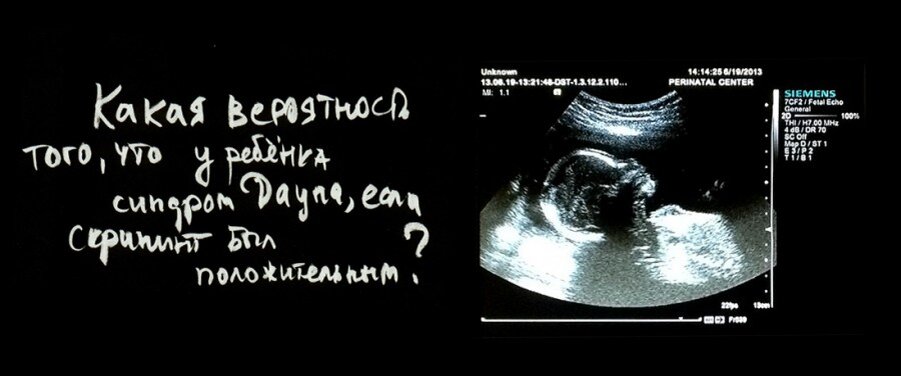

Беременность. Синдром Дауна или нет?

Назвали мою фамилию, я зашла в кабинет, легла. Намазали меня и водят по животу. Узистка оказалась совсем неразговорчивой и грубой. Сказала, что если хочу, чтобы со мной поговорили, могу пройти в частную клинику, а она только плод замеряет, все вопросы к своему доктору. Ничего я от неё хорошего не добилась, но пока вытиралась и одевалась, она сказала, что после УЗИ мне надо зайти ещё в один кабинет, пусть врач посмотрит результаты. Назвала мне номер кабинета и я пошла. Подхожу к нужной двери, а там закрыто на 30 минут, и вывеска висит.. врач-генетик.. Что я почувствовала, я даже описать не могу. Ребенок живой, растёт. Зачем меня направили к генетику?

Я вышла на улицу, чтобы немного прийти в себя. Присела на лавочку и, конечно, полезла в интернет, изучая результаты, записанные на УЗИ. Да носовая кость коротковата. Минимальный допустимый размер на этом сроке - 2,0 мм, а у нас 1,6 мм.

Немного перекусив и успокоившись, я пошла к врачу. В кабинете сидела приветливая доктор, которая меня всячески подбадривала. Она мне объяснила, что пока диагнозы ставить рано. По крови никаких отклонений она не видит, а на втором УЗИ все измерения могут встать в пределы нормы. Мы договорились, что когда я приеду делать второй скрининг, я также с результатами приду к ней на приём. Если и во второй раз будут подозрения, то можно сделать забор околоплодных вод для хромосомного анализа.. Но это уже крайние меры, а она уверена, что всё будет хорошо!